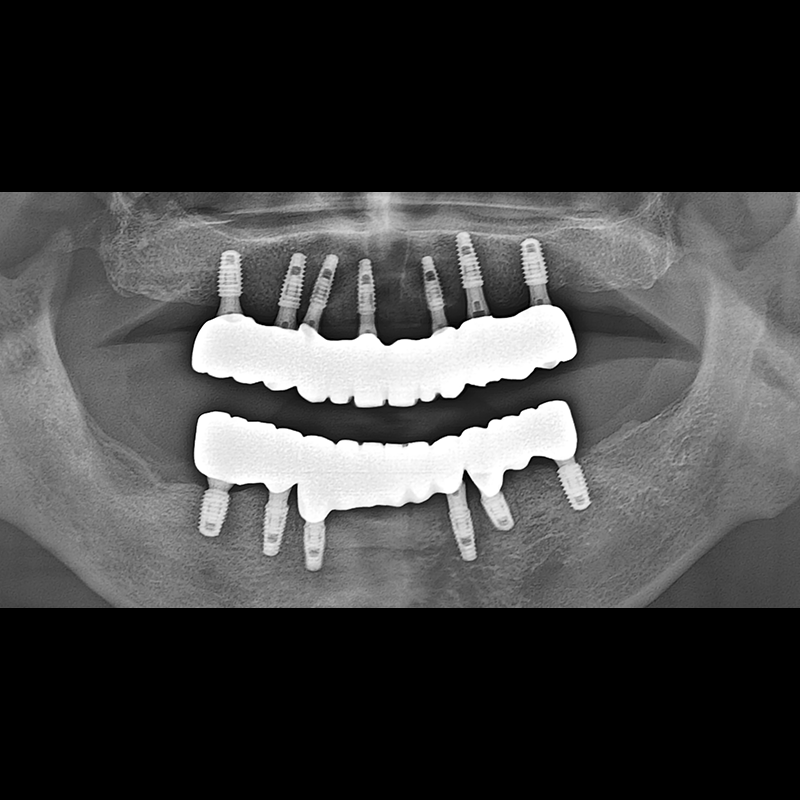

IMPLANT

BEFORE AFTER